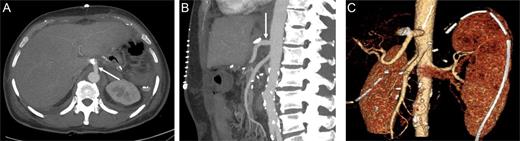

Preoperative computer tomography, mass (arrow) located in corpus of the pancreas.

At this point, the patient was recommended for further investigation in the Interventional Radiological Department for both diagnosis confirmation and, most importantly, to provide an opportunity for stenting the celiac trunk. In order to accomplish this, gastro-duodenostomy, choledoco-choledocostomy (anastomosis between the resected common bile duct) and jejuno-jejunostomy re-anastomosis were performed, and a temporary abdominal closure was done. The patient was taken to the Radiological Department. CT and angiography (Figs 2 and 3) showed that there was a narrowing part of the celiac trunk, and distal to this part, there was an occlusion (high degree of stenosis) of the celiac artery. In addition, retrograde filling of the GDA could be appreciated through the patent SMA (Fig. 3). A stent was considered impossible due to the high degree of stenosis that was a nearly total occlusion of the celiac trunk.

Contrast-enhanced CT in the arterial phase: axial (A) and sagittal (B) maximum intensity projections (MIP), and coronal oblique 3D volume-rendered (VR) images (C) demonstrating proximal celiac artery narrowing (arrow) due to compression by the median arcuate ligament. Downstream, an additional high-degree stenosis of the celiac trunk can be appreciated (dashed arrow).